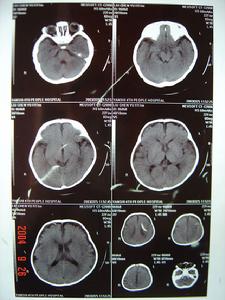

在嚴重的病例腦電圖檢查,可四川發現廣泛高度不正常的高波幅慢波及在此背景上的局灶性,改變相同影像學檢查(電子計算機斷層及磁共振檢查),可顯示腦水腫壞死灶(顳葉及額葉壞死灶見於單純皰疹腦炎)和主要基因位於腦白質的脫髓鞘病灶(急性播散性腦脊髓炎),